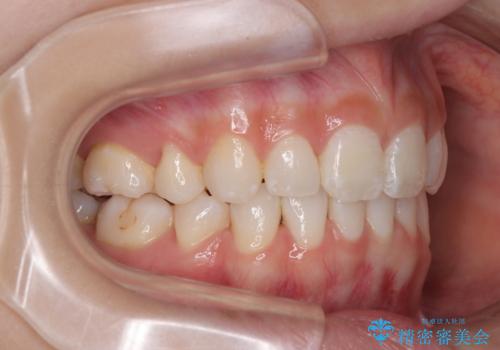

斜め前に飛び出した前歯 抜歯矯正で素敵な横顔に

下唇に前歯が当たって跡が残ってしまう状態でしたが、スッキリとした口元に仕上げることができました。

下顎はデコボコが気になっていたため、上下左右第一小臼歯4本を抜去して、ワイヤー装置にて口元の突出感を改善するよう矯正治療を行うこととしました。